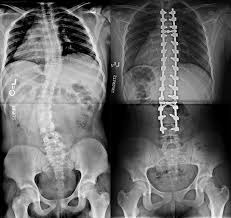

X-ray image of a scoliosis before surgery (left image) and after surgery using the traditional posterior approach with screws and metallic rods (right image).

The result of traditional scoliosis surgery is an irreversibly stiff spine that has lost its flexibility and ability to move, while the growth of the spine (and therefore also the trunk) of the patient is also irreversibly impaired.